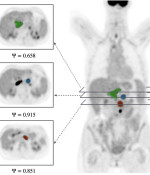

Synergistic interplay of morphology and metabolic activity rule response to CAR-T cells in B-cell lymphomas

Y Chen, S Sabir, C Kuttler, J Belmonte, A Martinez, L Martin, L Lopez-Corral, A Martin-Sancho, JC Cañadas, C Montes, M. PTamayo, A Cedillo, P Balsalobre, P Barba, A Pérez-Martínez, VM Pérez-García

arXiv:2505.11894